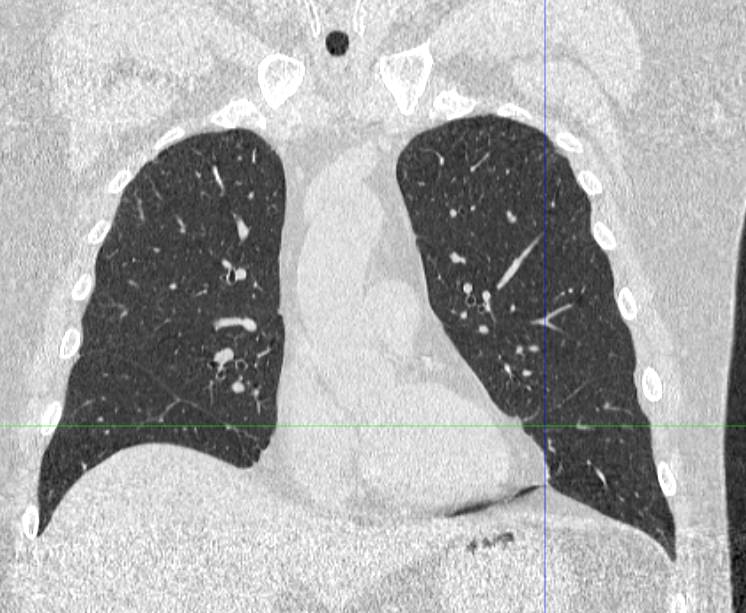

Во время исследования рентгеновская трубка томографа вращается вокруг исследуемой области и производит множество послойных снимков с шагом 0,5-1 мм. Полученные снимки поперечного сечения с помощью компьютерной программы могут быть преобразованы в 3D-изображения исследуемого органа или участка ткани. Это позволяет выявлять практически все заболевания легких на ранних стадиях и назначать своевременное лечение.

В медицинском центре «Доступная медицина» используется современный 128-срезовый компьютерный томограф TOSHIBA AQUILION CXL, на котором проводится сканирование легочной ткани. За счет увеличенного количества детекторов аппарат производит снимки с большой скоростью и минимальной дозой облучения. При этом инновационные цифровые приложения позволяют получить объемные изображения легочной ткани высокой четкости, контрастности и в мельчайших подробностях.